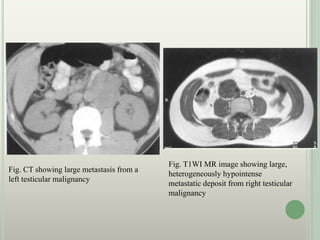

Fig. CT showing large metastasis from a

left testicular malignancy

Fig. T1WI MR image showing large,

heterogeneously hypointense

metastatic deposit from right testicular

malignancy